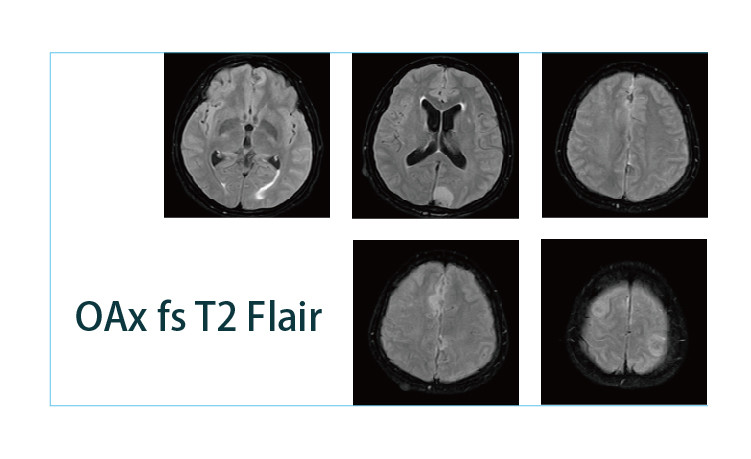

【朗润影像档案】磁共振影像病例分享(编号20190419)